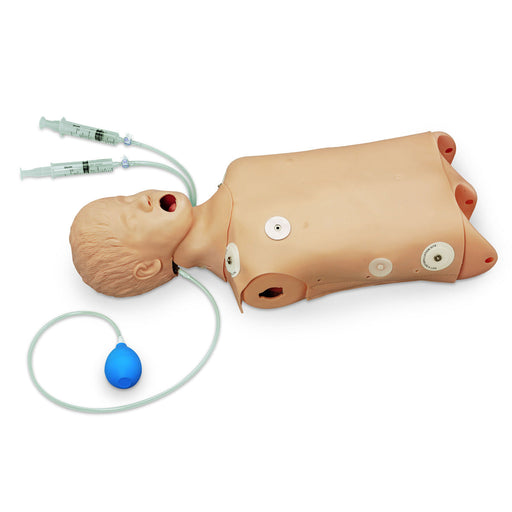

VascularAccessChild Femoral Replacement Tissue

The VascularAccessChild Femoral Replacement Tissue is an ultrasoundable soft tissue that allows users to develop their skills in complete pediatric central venous catheterization of the femoral vein.

Use ultrasound to visualize cannulation, guidewire threading, and catheter placement. Practice palpating external landmarks to identify vessel location for blind/landmark insertion approaches.

VascularAccessChild Femoral Replacement Tissue

- Anatomically correct, ultrasound compatible, femoral tissue with all relevant difficult palpating landmarks and vascular anatomy

- Market-leading durability—self-sealing tissues and veins provide value in the frequency of needle sticks and full catheterizations per access site

- Exceptional ultrasound imaging through repeated use—needle sticks and full catheterizations do not degrade the image acuity

- Red and blue simulated blood differentiate the arterial and venous vessels; provides immediate feedback on successful or unsuccessful cannulation

- Arterial pulse is present, and vein realistically compresses under palpation

- Easily adjust venous pressure regulator for vein compression or low-pressure simulation scenarios

- Replaceable tissues come pre-filled with blue venous and red arterial fluid

- Tissues can remain filled when not in use and are easy to refill with fluid when necessary